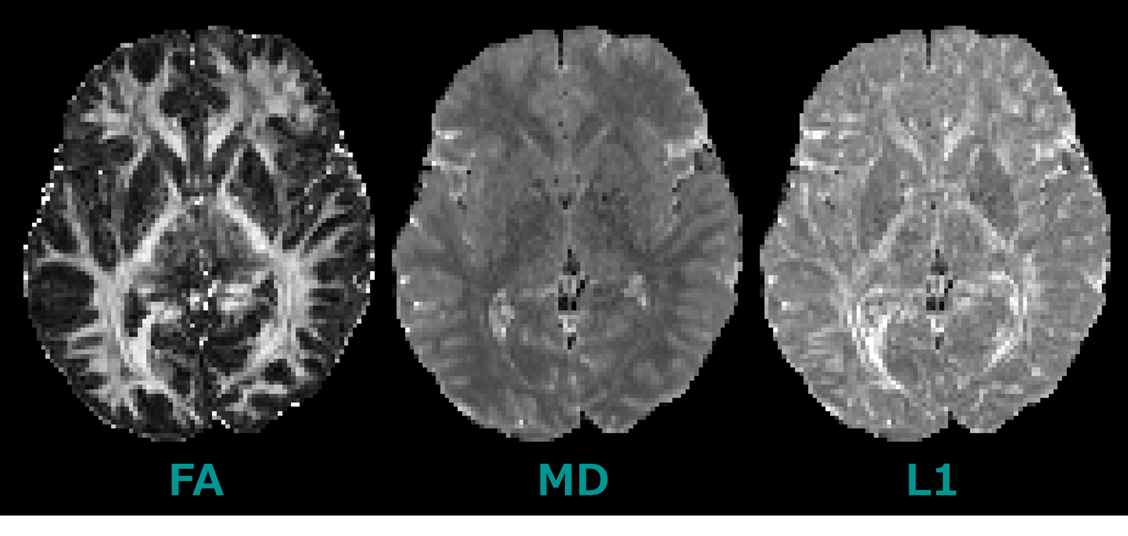

FSL】FSLを用いた拡散テンソルイメージング: DTI | K-Lab

FSL】FSLを用いた拡散テンソルイメージング: DTI | K-Lab,DIPY】DIPYを用いた拡散テンソルイメージング: DTI | K-Lab,Diffusion MRI, also referred to as diffusion tensor imaging or DTI, of the human brainの写真素材 [FYI03525945] | ストックフォトの Qlean Market(キュリンマーケット),Amazon.co.jp: Diffusion Tensor Imaging: A Practical Handbook (English Edition) 電子書籍: Van Hecke, Wim, Emsell, Louise, Sunaert, Stefan: 洋書,Diffusion MRI measurements in challenging head and brain regions via cross-term spatiotemporally encoding | Scientific Reports

![Diffusion MRI, also referred to as diffusion tensor imaging or DTI, of the human brainの写真素材 [FYI03525945] | ストックフォトの Qlean Market(キュリンマーケット) Diffusion MRI, also referred to as diffusion tensor imaging or DTI, of the human brainの写真素材 [FYI03525945] | ストックフォトの Qlean Market(キュリンマーケット)](https://cdn.qleanmarket.amanaimages.com/uploads/items/035/259/45/preview/FYI03525945.jpg)